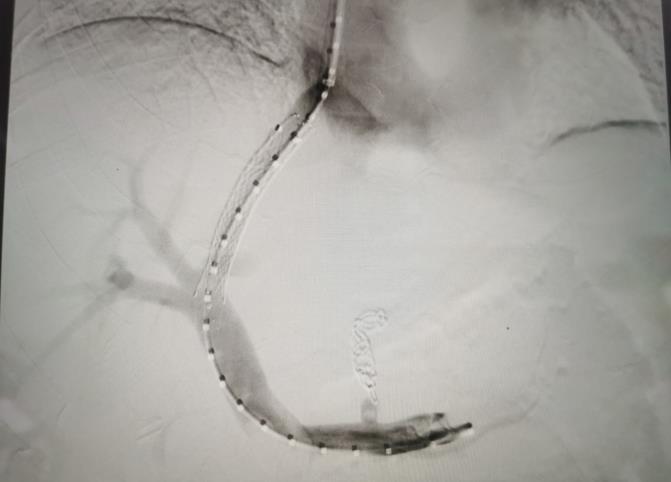

經(jīng)過我院血管介入科醫(yī)療團隊的精心準備,患者在數(shù)字減影血管造影機(DSA)導(dǎo)引下,順利經(jīng)頸靜脈入路進入下腔靜脈并成功穿刺了門靜脈右支主干,術(shù)中栓塞了曲張的胃冠狀靜脈-食管靜脈叢將支架植入肝實質(zhì)內(nèi),支架兩端分別置于門靜脈和肝靜脈內(nèi),術(shù)程歷時2小時,術(shù)中患者時刻保持清醒,手術(shù)切口僅5毫米,術(shù)后第2天恢復(fù)飲食,腹脹、腹水癥狀明顯好轉(zhuǎn),未出現(xiàn)嘔血、黑便及肝性腦病等并發(fā)癥,術(shù)后第3天康復(fù)出院。